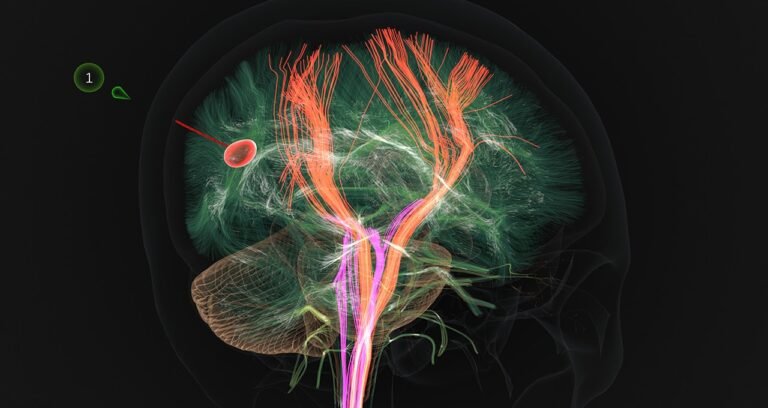

Atlas Meditech’s Pathfinder software program is integrating AI algorithms that may recommend secure surgical pathways for specialists to navigate via the mind to succeed in a lesion.

A key good thing about Atlas Meditech’s superior simulations — both onscreen or in immersive digital actuality — is the power to customise the simulations, in order that surgeons can follow on a digital mind that matches the affected person’s mind in measurement, form and lesion place.

“Each affected person’s anatomy is a bit completely different,” mentioned Dr. Cohen-Gadol. “What we are able to do now with physics and superior graphics is create a patient-specific mannequin of the mind and work with it to see and just about function on a tumor. The accuracy of the bodily properties helps to recreate the expertise we now have in the true world throughout an operation.”

With a segmented view of a affected person’s mind, Atlas Pathfinder can regulate its 3D mind mannequin to morph to the affected person’s particular anatomy, capturing how the tumor deforms the traditional construction of their mind tissue.

Primarily based on the visualization — which radiologists and surgeons can modify to enhance the precision — Atlas Pathfinder suggests the most secure surgical approaches to entry and take away a tumor with out harming different elements of the mind. Every strategy hyperlinks out to the Atlas web site, which features a written tutorial of the operative plan.

“AI-powered determination help could make a giant distinction in navigating a extremely advanced 3D construction the place each millimeter is essential,” Dr. Cohen-Gadol mentioned.

Utilizing a VR headset, surgeons will have the ability to work inside this digital surroundings, going step-by-step via the process and receiving suggestions on how carefully they’re adhering to the goal pathway to succeed in the tumor. AI algorithms can be utilized to foretell how mind tissue would shift as a surgeon makes use of medical devices in the course of the operation, and apply that estimated shift to the simulated mind.